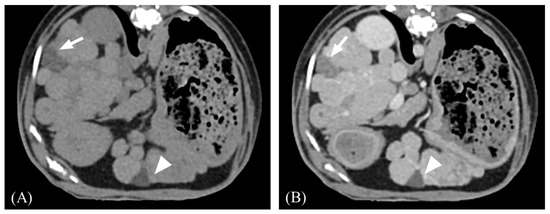

3.2. Qualitative Computed Tomographic Features